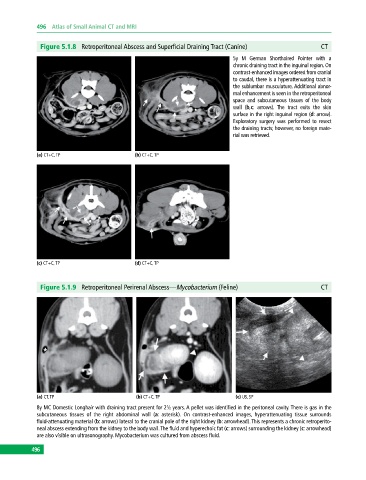

Figure 5.1.8 Retroperitoneal Abscess and Superficial Draining Tract (Canine) CT

5y M German Shorthaired Pointer with a

chronic draining tract in the inguinal region. On

contrast‐enhanced images ordered from cranial

to caudal, there is a hyperattenuating tract in

the sublumbar musculature. Additional abnor

mal enhancement is seen in the retroperitoneal

space and subcutaneous tissues of the body

wall (b,c: arrows). The tract exits the skin

surface in the right inguinal region (d: arrow).

Exploratory surgery was performed to resect

the draining tracts; however, no foreign mate

rial was retrieved.

(a) CT+C, TP (b) CT+C, TP

(c) CT+C, TP (d) CT+C, TP

Figure 5.1.9 Retroperitoneal Perirenal Abscess—Mycobacterium (Feline) CT

(a) CT, TP (b) CT+C, TP (c) US, SP

8y MC Domestic Longhair with draining tract present for 2½ years. A pellet was identified in the peritoneal cavity. There is gas in the

subcutaneous tissues of the right abdominal wall (a: asterisk). On contrast‐enhanced images, hyperattenuating tissue surrounds

fluid‐attenuating material (b: arrows) lateral to the cranial pole of the right kidney (b: arrowhead). This represents a chronic retroperito

neal abscess extending from the kidney to the body wall. The fluid and hyperechoic fat (c: arrows) surrounding the kidney (c: arrowhead)

are also visible on ultrasonography. Mycobacterium was cultured from abscess fluid.